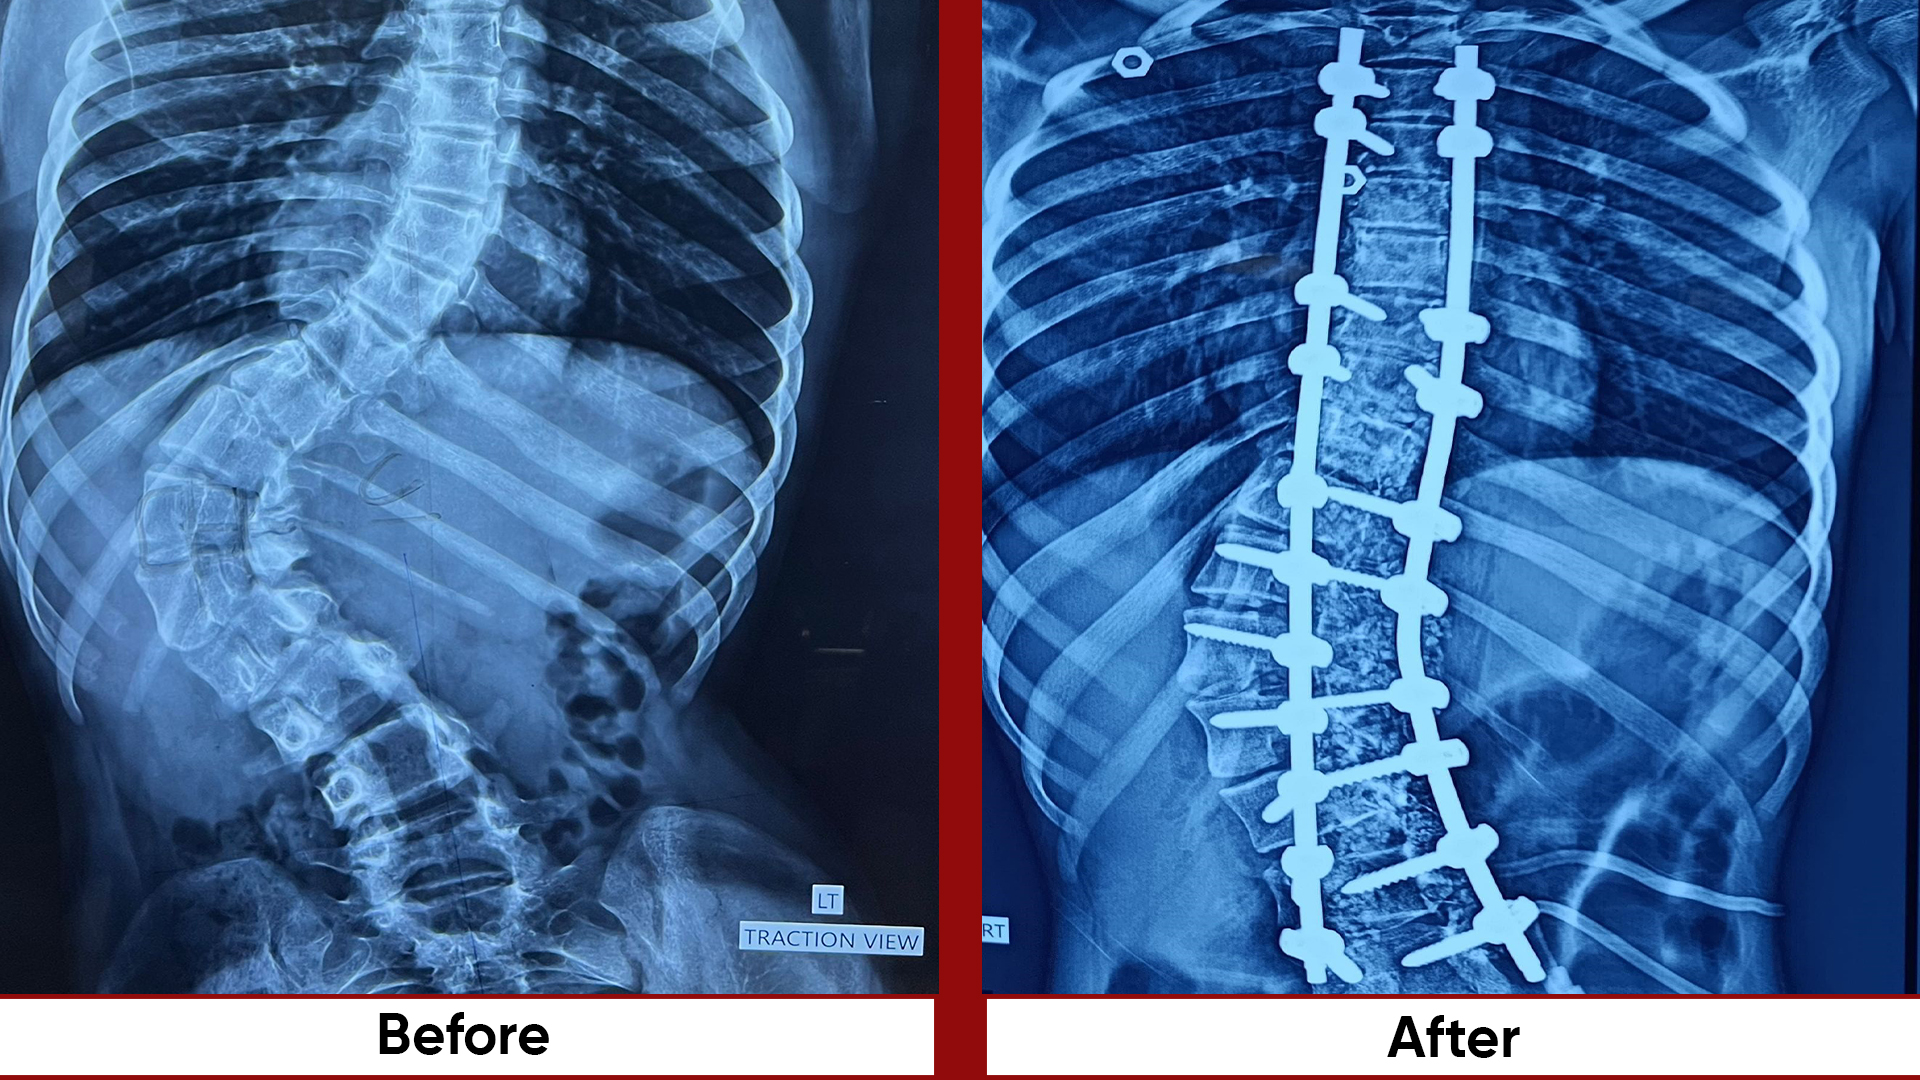

• Spine: Trauma Deformity –EOS AIS-Adult deformity, all fractures operated within 24/7.

• Deformity Correction (limb lengthening, bowlegs, knock knees)